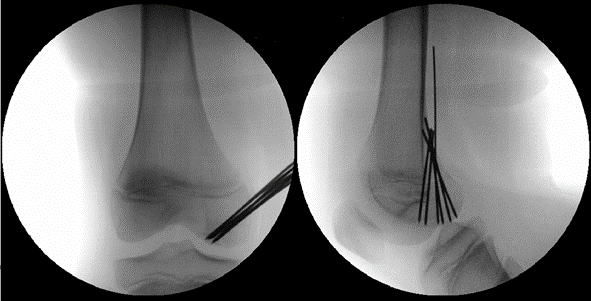

Die Operation kann minimalinvasiv durchgeführt werden. Manchmal kann das Kreuzband genäht werden. Es muss aber meistens durch ein eigenes Sehnentransplantat (Hamstrings) ersetzt werden. Im Anschluss beginnt die Rehabilitation in enger Zusammenarbeit mit der Physiotherapie. In dieser Zeit muss eine Sportpause eingehalten werden. Zeigt sich in den Nachkontrollen ein guter Fortschritt, also gute Muskulatur und ein stabiles Gelenk, kann in den meisten Fällen nach 9 bis 12 Monaten mit Kontaktsportarten wieder begonnen werden. Die Sonderform des Eminentiaausrisses wird, beim jüngeren Kind, je nach Dislokationsgrad entweder konservativ mit Gips oder operativer Refixierung des Fragments behandelt.

Meniskusverletzungen bei Kindern sind deutlich seltener als bei Erwachsenen. Eine typische Ursache für traumatische Meniskusverletzungen ist die Verdrehung des Kniegelenkes unter Belastung. Skifahren oder Fussball sind beispielsweise Sportarten mit einem erhöhten Risiko. Akute, verletzungsbedingte Meniskusrisse äussern sich durch Schwellung sowie Schmerzen oder Blockaden vor allem bei Dreh- und Beugebewegungen des Kniegelenkes. Die Behandlungsoptionen sind vergleichbar mit den der Erwachsenen. Liegt tatsächlich eine Meniskusverletzung vor, kann diese meistens arthroskopisch versorgt werden. Sehen wir eine Möglichkeit, den Meniskus zu erhalten, dann wird dieser genäht. Damit das verletzte Knorpelgewebe heilen kann, muss es je nach Rissform durch eine Schiene vor zu viel Bewegung und durch Krücken vor zu viel Belastung für 4 bis 6 Wochen geschützt werden. Kontaktsportarten müssen nach einer Meniskusnaht für circa 6 Monate ausgesetzt werden. Eine Sonderform stellt der Scheibenmeniskus dar. Hierbei handelt es sich um eine angeborene fehlerhafte Meniskusform, statt halbmondförmig ist er scheibenförmig. Dies führt eher selten zu Problemen, kann aber zu einem störenden Schnappphänomen führen. Auch diese Fehlform kann bei Beschwerden mittels Gelenkspiegelung korrigiert werden.